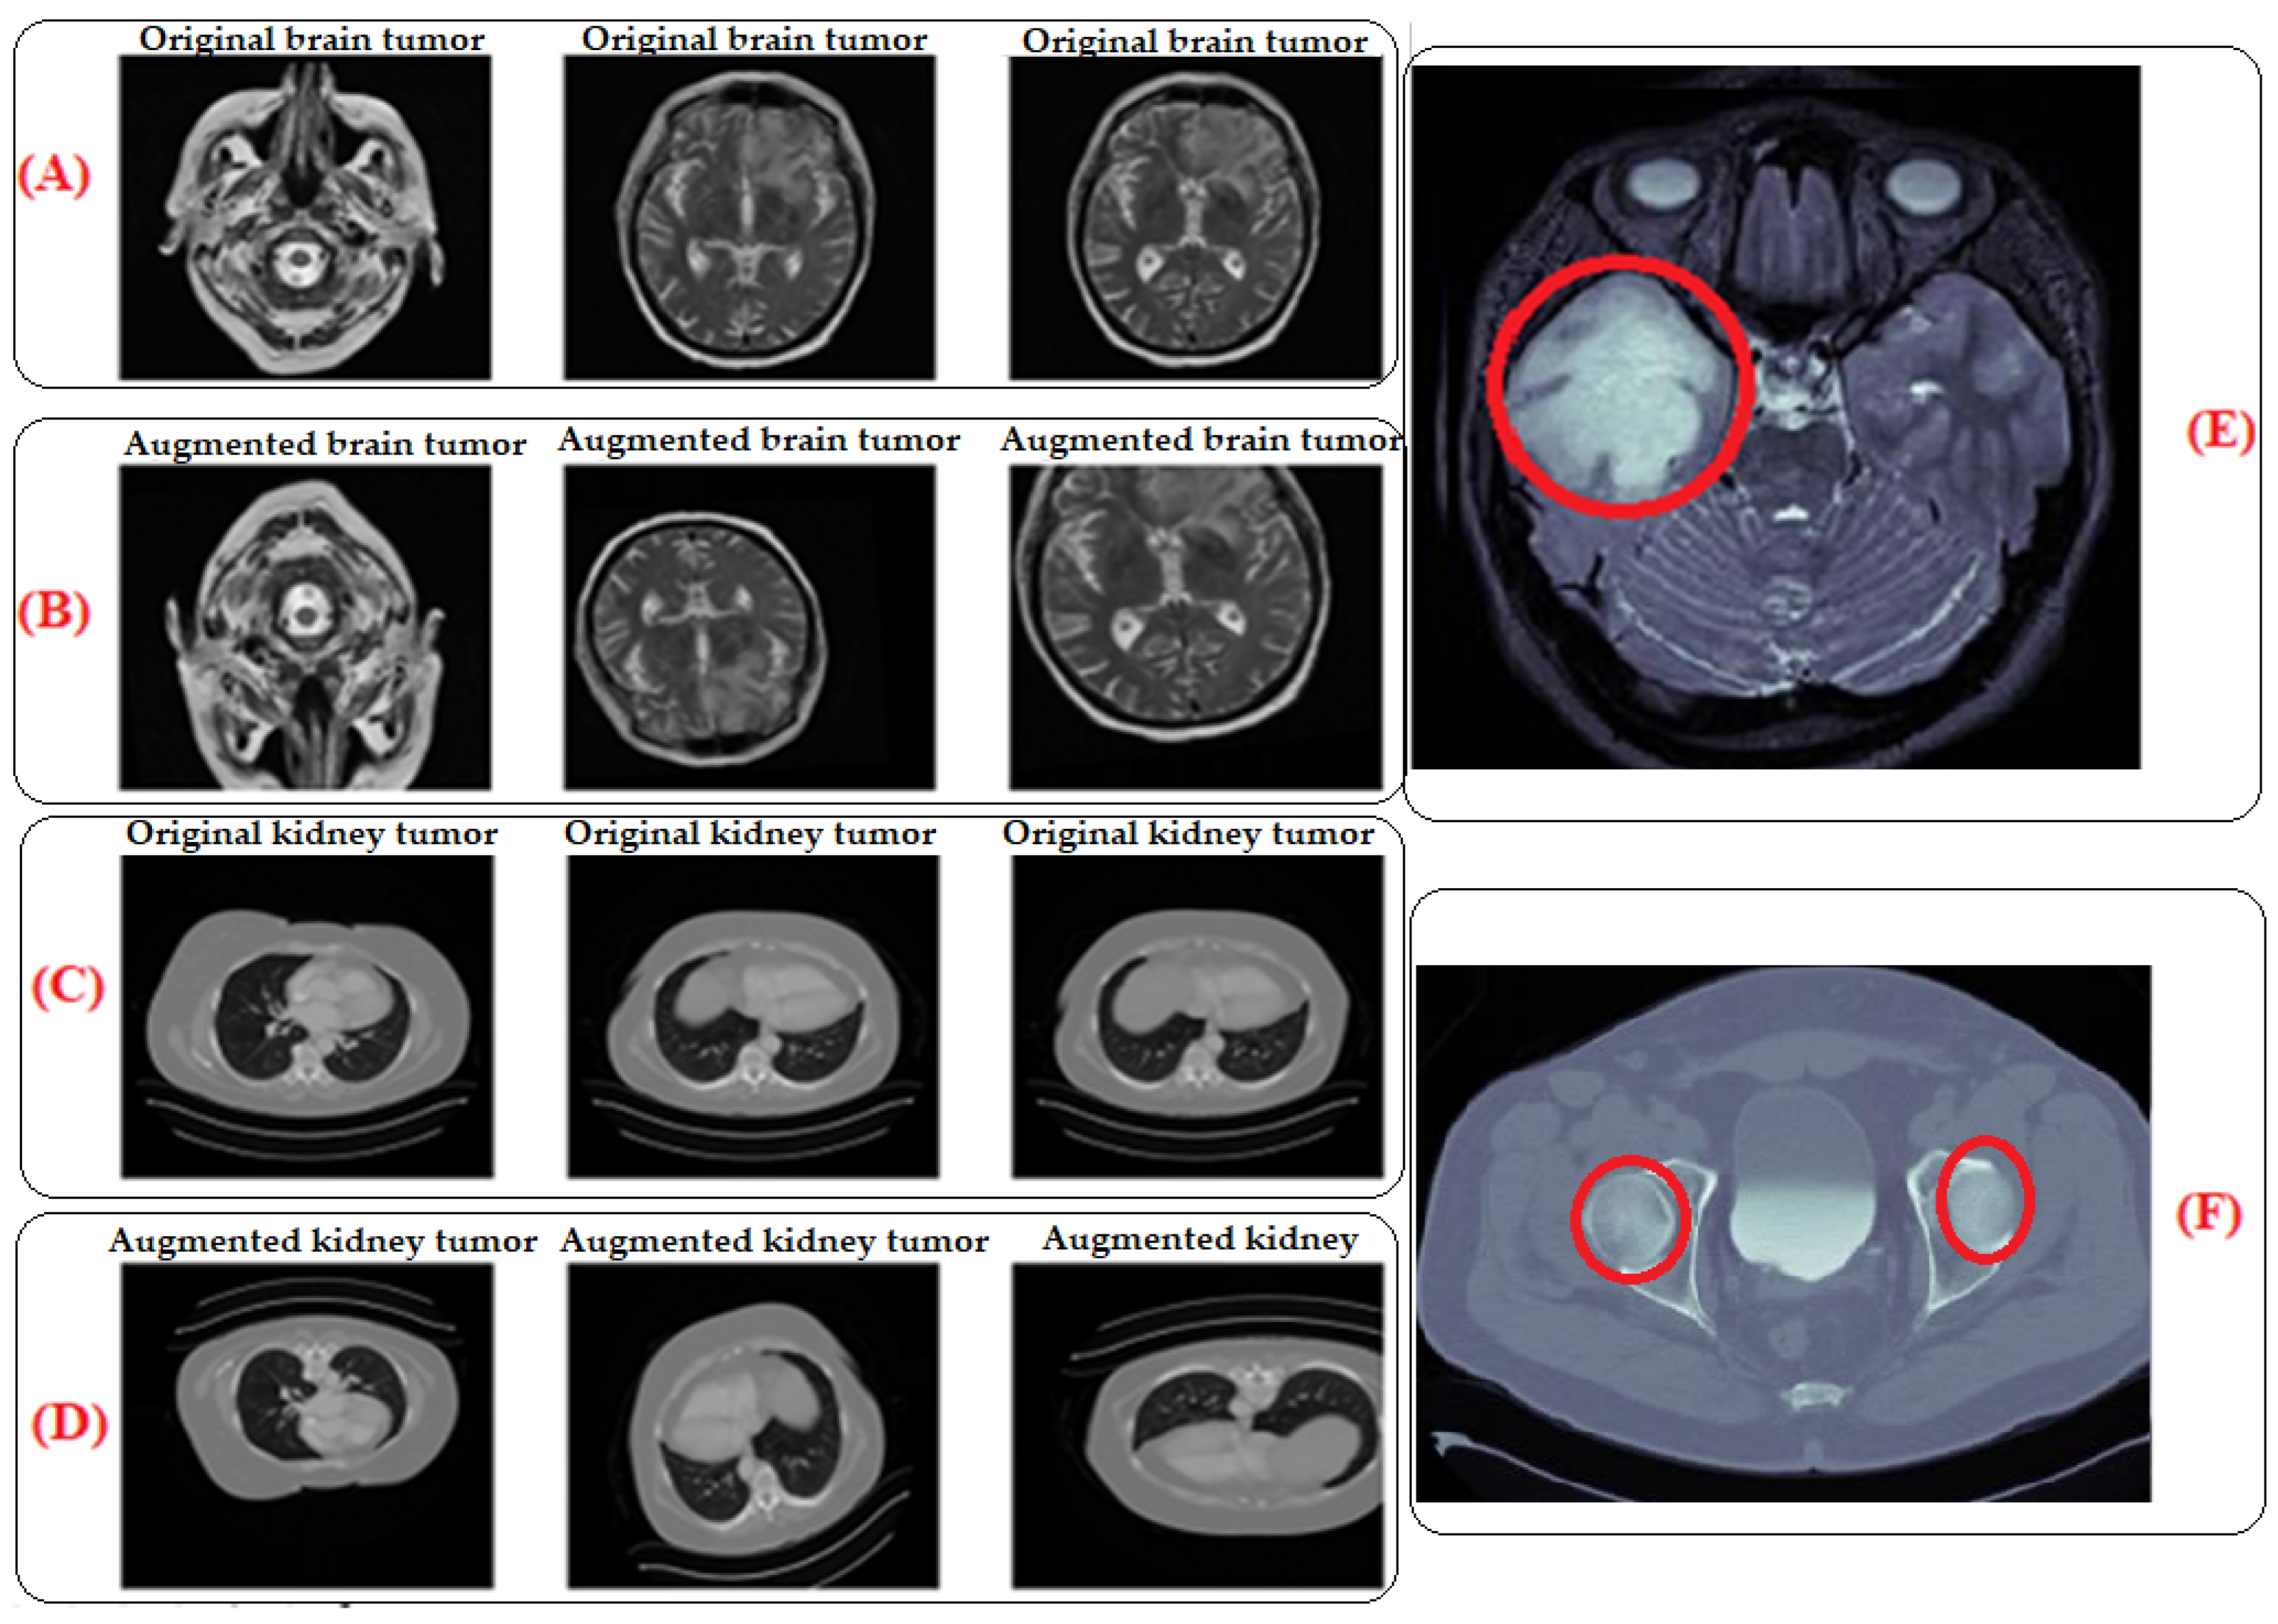

3.3. Traditional Data Augmentation Techniques

By subjecting the model to a wider range of variations and scenarios, traditional data augmentation techniques were utilized to expand the size and diversity of our training dataset and improve the model’s robustness [6,50]. This entails using different transformations, such as flipping, shifting, rotating, or zooming, on the current data to produce new training examples that are marginally different from the initial ones, as Table 2 illustrates. By adding more data, the model’s sensitivity to noise or tiny changes in the input data is reduced, improving the generalization performance, as seen in Figure 2. The area circled in the red color shows the tumors. The images in (E) for the brain and (F) for the kidney are the zoomed-in images that show the areas where the tumors are located. (E) represents a zoomed-in view of an augmented brain tumor image and allows for a detailed examination of the specific region where the tumor is located. This zoomed-in view provides insights into how the augmentation process affects the detailed features of the tumor in the image. Similar to part E, (F) shows the augmented kidney tumor image (MRI), which contributes to the diversity of the training dataset for kidney tumor images. (A) The original brain tumor image (MRI) represents the original MRI scan focused on the brain, specifically showcasing a tumor. It is the unaltered, initial image used in the training dataset. (B) The augmented brain tumor image (MRI) corresponds to the image of the brain tumor that underwent traditional data augmentation techniques. These techniques involved applying various transformations like flipping, shifting, rotating, or zooming to create slightly different versions of the original image. Part B displays the augmented version, contributing to an expanded and more diverse training dataset. (C) The original kidney tumor image (MRI) represents the original unaltered MRI scan focused on the kidney, specifically showcasing a tumor. (D) The augmented brain tumor image (MRI) corresponds to the image of the kidney tumor that underwent traditional data augmentation techniques.

Figure 2.

MRI images of original and augmented brain and kidney tumor data. The area circled in red color delineates the tumors. (A): Original brain tumor image (This represents the unaltered, initial image used in the training dataset, (B): Augmented brain tumor image (This corresponds to the image of the brain image that has undergone traditional data augmentation techniques), (C): Original kidney tumor image (This represents the original unaltered MRI scan focused on the kidney, (D): Augmented brain tumor image (This corresponds to the image of the kidney tumor, that has undergone traditional data augmentation techniques. (E): Magnified view of augmented brain tumor image, (F): Magnified view of augmented kidney tumor image.

To prevent overfitting, which occurs when a model memorizes training data instead of discovering significant patterns, data augmentation is essential. Through data augmentation, randomness and variability are added, making it less likely for the model to overfit and allowing it to develop more reliable and broadly applicable representations [6,51]. We used shear transformations within a maximum shear angle, channel shifting within a specified range, zooming in or out via a specified range, rotation within a certain angle, zero component analysis (ZCA) whitening (disabled in our case), horizontal and vertical flips to mirror images, and width and height shifts to randomly shift images within a fraction of their total width or height. These scales or ranges give the freedom to regulate the degree of transformations used during data augmentation, enabling the customization of the augmentation procedure to the particular needs of the dataset and the deep learning task.